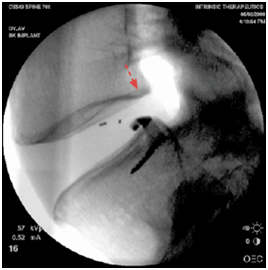

После операции при рентгенологическом контроле определяется положение Баррикада в области дефекта фиброзного кольца. Рис.7.

Рис.7. Рентгенограмма поясничного отдела позвоночника. Стрелкой показано положение Баррикада в межпозвонковом диске. |